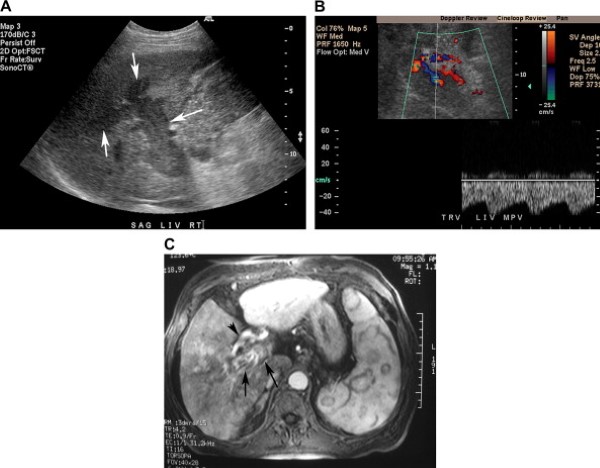

Đối với các bệnh nhân xơ gan hoặc nghi ngờ có u gan ác tính, việc phân biệt giữa huyết khối đơn thuần và huyết khối ác tính là bắt buộc. Chứng minh dòng chảy lìa gan có nhịp động mạch bên trong huyết khối của tĩnh mạch cửa có độ nhậy vừa phải (62%) nhưng độ đặc hiệu cao (95%) trong chẩn đoán huyết khối ác tính tĩnh mạch cửa (Hình 17) [7,8]. Phân biệt huyết khối lành tính với huyết khối ác tính là chủ chốt để tiên lượng bệnh và chọn bệnh nhân cho phẫu thuật. Nếu cần thiết, người ta có thể chọc hút kim nhỏ huyết khối tĩnh mạch cửa dưới hướng dẫn siêu âm để thiết lập chẩn đoán [9].

Hình 17. Huyết khối ác tính tĩnh mạch cửa ở bệnh nhân nam 72 tuổi có tiền sử ung thư biểu mô tế bào gan. Chọc hút kim nhỏ huyết khối tĩnh mạch cửa xác định huyết khối là ung thư biểu mô tế bào gan. (Hình A) Ảnh siêu âm thang xám ở rốn gan phát hiện tổ chức giảm âm lấp đầy và gây giãn lòng tĩnh mạch cửa và các nhánh của nó (các mũi tên). (Hình B) Ảnh siêu âm Doppler và màu chứng minh tình trạng có mạch máu bên trong huyết khối. Dạng sóng động mạch sức cản thấp gợi ý huyết khối ác tính do u. (Hình C) Ảnh cộng hưởng từ tiêm thuốc đối quang, thì động mạch cho thấy ngấm thuốc ngoằn ngoèo ở trong huyết khối tĩnh majhc (mũi tên), cho phép xác định huyết khối ác tính. Lưu ý động mạch gan (đầu mũi tên) ngấm thuốc mạnh, hiện rõ.